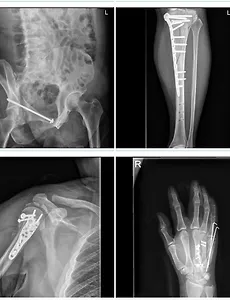

반응형 전체 글1472 병신 vs 병신... 오늘 아내와 코스트코에서 장보던 중에 아내가 다른 물건 집으러 먼저가고 내가 천천히 따라가는데 갑자기 부러진 왼쪽 무릎이 뒤틀리는 고통과 발 뒷꿈치에 통증이 왔다. 뒤에서 따라오던 카트가 내 발뒷꿈치를 쳤다.가해자는 사과도 없이 옆으로 비켜서서 "어머 아프겠네" 이러고 걍 빤히 쳐다만 본다. 통증 때문에 그사람들 소리도 제대로 들리지 않았다.부딪혔으면 사과라도 먼저해야 하는거 아닌가?성질이 났지만... 예전에 몸이 정상일 때 코스트코에서 장볼 때 카트로 발을 치는 사람에게 승질 냈다가 아내가 싫어했던 기억이 떠올라 어떻게든 통증이나 다스리려고 노력했지만 한켠으로 수술한 무릎이 어떻게 되는건 아닌가 싶어 걱정도 되어서 가해자에게 연락처를 물었다.반바지를 입고 보조기를 차고 있었으니... 그 크나큰 흉터와 .. 2017. 9. 8. 2017 교육공무원 봉급표 월보수액 현실적인 초등교사 월급표 중등고등학교교사 실수령액표 2017 교육공무원 봉급표 월보수액 현실적인 초등교사 중등고등학교교사 실수령액표 보통 정교사들은 9호봉부터 시작합니다. 임용시 호봉획정 때 교육대학을 다닌 기간을 호봉에 산정해주는것인데요. 교사 호봉표의 마지막은 40호봉입니다. 40호봉 되면 퇴직해라 이 뜻은 아니구요. 웬만하면 교대 나와서 임용되서 정년퇴직이 될 때까지 40호봉을 넘기는 쉽지 않은 이유 뿐입니다. 교사가 최고의 인기 직종으로 각광받는 것은 정시 출근 정시 퇴근 그리고 여름방학 겨울방학이 존재하는것이고 여자들의 경우 육아휴직이 완벽하게 이루어지는 이유등이 있겠습니다. 각광받는 이유중에서 무엇보다 중요한 것이 바로 교원 연금입니다. 지금 연금을 받는 퇴직자분들을 보면 한달에 300만원 가까운 금액을 수령하는데... (저희 어머님 같은 경우.. 2017. 9. 3. 화제의 원조 하늘보리녀 이태임 2015.07.10 00:33 재작년에 sam_3242라는 파일명이 잠깐 뜬 적이 있었는데, 그 때 반사적으로 주목받은 키워드가 하늘보리녀였다. 화제의 하늘보리녀라는 제목의 동영상은 국내 일반인의 유출 동영상. 음~~~ 인상 깊게도 화면의 상당부분에 하늘보리 음료수가 비춰지기 때문에 하늘보리녀라고 불렸다지? 봤냐구? 글쎄~~~ 구글에서 "하늘보리녀"라고 치면 이미지는 나오긴하다. 동영상은 불법이니까^^: 대신에 안구 정화들 하시라고 원조 하늘보리녀인 이태임의 하늘보리 CF사진으로 만족 ^^; 예원하고 욕설 반말 때문에 칩거에 들어가서 상대적으로 피해보고 있는 이태임씨가 빨리 복귀하면 좋겠넹... 요즘은 복귀해서 활동중이긴 한데...활발하지가 않아서...좀더 많이 나오길... 봐~ 하늘보리 딱~ 들고 있지.. 2017. 8. 24. GS25편의점에서 파는 식충식물 파리지옥. 우리집 리옥이 편의점이 경쟁이 치열해지니까 별의별걸 다 팔더니...급기야 이런 것도 팔고 있을지 처음 알았다.바로 파리지옥이다.우리집에 들어오는 식물은 살아나가는 식물이 없다.그 죽이기 힘들다는 부겐빌레아가 내가 병원에 입원해 있는 동안에 바짝 말라 죽었다.하긴 뭐...아내도 회사다니면서 내 병수발 들려니, 화분 따위에 신경쓸 여력은 없었을테니까....그래서 편의점에서 파리지옥을 파는 것을 보았을 떄 충동구매를 하고 싶었지만 갈들을 하긴 했다.하지만 6천원이라는 생각보다 저렴(?) 한 가격에 덜컥 구입을 해 버렸다.집에 이 아이를 데려오자마자 아내에게 카톡을 보냈다.파리지옥에서 "리지"만 따서 이름을 지어주었다고 보냈다.퇴근해서 집에 온 아내가 리지 말고 "리옥"이라고 바꾸자고 제안했다.리옥이가 왠지 좀 더 친근하게 .. 2017. 8. 21. 생활의달인 맛집 신월동 중국집 미스차이나 집근처에 식당은 참 많이 있는데...방송에 나온 맛집은 별로 없다.그나마 조금 가까이 있는 곳이 신월4동에 있는 미스차이나 라는 중국식당이다.생생정보 같은 곳에 소개되는 맛집은 잠깐 반짝 유명하지만 생활의달인에 소개되는 식당은 2달 이상은 줄을 서야 하는 편이다.미스차이나도 처음 생활의달인에 소개되었을 때는 방문할 엄두를 못냈다.미스차이나 근처에 있는 신월4동 정보화도서관에 책 빌리러 갈 때 지나치다보면 항상 줄이 서 있었다.그런데 요즘은 많이 잊혀진 모양이다.중국집 메뉴 가격대를 정확히 잘 모르겠지만, 크게 비싼 것 같지는 않은데...비싼 메뉴는 터무니없이 비싸보이긴 하다.요즘 백종원의 푸드트럭에서 백선생이 "잘될때 음식값을 내려라" 라고 말이다.맛집으로 유명세를 타는 식당들 보면 소개되서 잘될 때 가.. 2017. 8. 20. 만정바다낚시터 민어낚시채비. 민어요리법 민어지리탕 친구와 밤 낚시를 다녀왔어요. 2016.08.12 22:33 사실 저하고 별로 궁합이 맞지 않아서 맨날 꽝만 치던 영종도 정성바다낚시터에 민어낚시를 하러 다녀왔어요. 요즘 유료바다낚시터레서는 여름 보양식으로 인기 많은 민어낚시가 유행인데요. 만정레저바다낚시터도 민어가 방류되어 있어서 민어 노리시는 분들이 많더군요. 만정에서 민어포인트로 유명한 곳은 바로 저 위의 사진에 보이는 수차 라인에서 섬 앞쪽 까지인데요. 특좌대 방갈로 1번부터 3번에 해당합니다. 저희는 자리가 없어서 특방갈로6번에 들어갈 수 있었어요. 그나마도 다행이었죠. 저는 오히려 수차 뒷쪽 15미터지점을 노려서 수차까지 흘리면서 탐색했어요. 새벽 3시쯤 히트. 3.2kg의 건강한 민어가 잡혔네요. 민어는 양식민어지만 맛은 참민어 못지 않게 .. 2017. 8. 18. 이전 1 ··· 40 41 42 43 44 45 46 ··· 246 다음 반응형